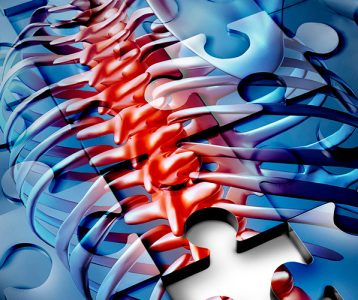

Os desvios da coluna, caracterizados por curvaturas anormais da estrutura vertebral, se apresentam de diferentes formas e perfil populacional. Essas condições podem causar diversos impactos na saúde, por exemplo, dor e cansaço. Além disso, tendem a levar a conflitos na autoestima nos casos em que se tornam aparentes. No entanto, todos esses problemas podem ser tratados por médicos especialistas de acordo com o grau e a severidade.

Tipos e causas dos desvios

Toda coluna saudável tem um leve grau de curvatura para dar mobilidade à estrutura e ao tronco corporal como um todo. Sendo assim, os problemas ocorrem quando estas curvaturas anormais da estrutura vertebral são acentuadas. Esses desvios, que dependem da região, envolvem escoliose, hipercifose e hiperlordose.

Na escoliose ocorre um desvio acentuado da coluna para os lados, formando um S (ao ver a pessoa de costas). Na hiperlordose, a acentuação se dá para a frente, na altura da região lombar, causando a proeminência dos glúteos. Enquanto na hipercifose ocorre um aumento anormal da curvatura da região cervical, no alto da coluna.

As manifestações mais visíveis envolvem ombros em alturas desiguais e um seio mais proeminente que o outro em mulheres. Também é comum a desproporção da curva do tronco – especialmente na região que vai do peito para a lombar – e a curva acentuada na altura da cervical, a popular corcunda.

Em casos mais acentuados podem ocorrer quadros de dor, frequentemente relacionada à tensão muscular induzida pela curva – com a possibilidade de ser intermitente ou persistente. Ademais, esses indivíduos podem reportar fadiga muscular devido à constante tensão e limitação da amplitude de movimento, o que pode tornar a realização de atividades cotidianas mais desafiadoras.

“O tratamento deve ser personalizado, levando em consideração a sintomatologia e grau do desvio”, ensina o médico. Entretanto, em geral, a primeira abordagem é a fisioterapia, que envolve exercícios específicos para fortalecer os músculos das costas, melhorar a postura e reduzir a dor.

Além disso, dispositivos ortopédicos como coletes podem ser prescritos para ajudar na correção da postura em casos mais evoluídos. Em quadros de curvaturas muito acentuadas e sintomas visíveis e debilitantes, as cirurgias de correção são indicadas. Um exemplo é a artrodese, intervenção que realiza a fusão das vértebras afetadas pelo desvio por meio de parafusos e hastes, mantendo-as na posição correta. Já na osteotomia são realizados cortes controlados nas vértebras para reposicioná-las.